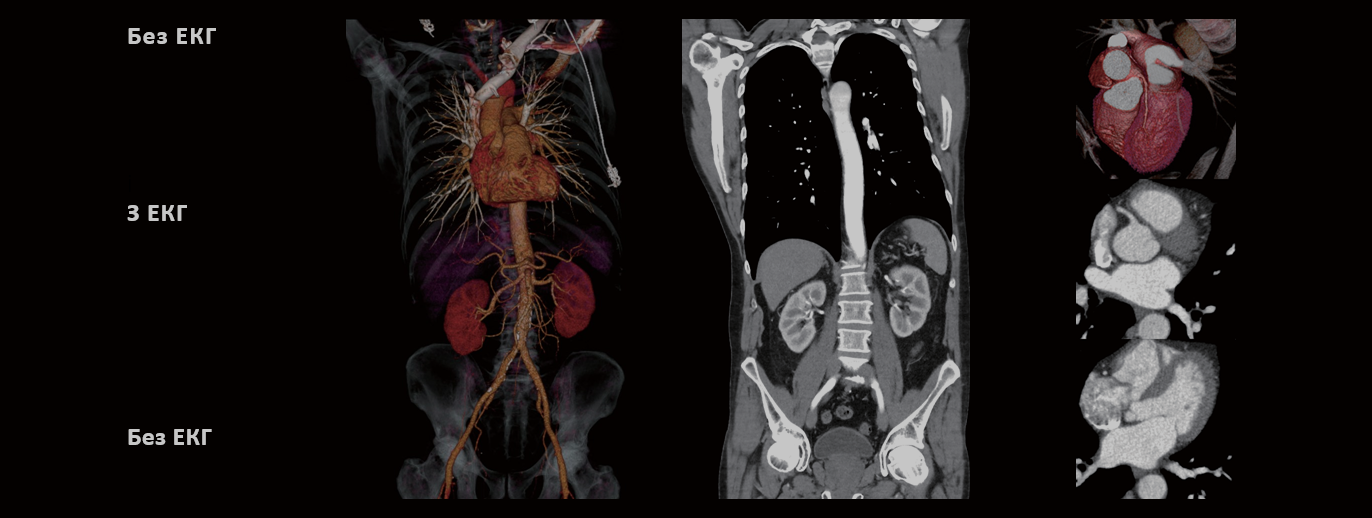

Для виключення розшарування аорти була отримана безшовна візуалізація всієї аорти від дуги  до стегнових артерій. ЕКГ-зображення серця та кореня аорти дозволило впевнено виключити патологію клапанів та обструктивну хворобу коронарних артерій. Пацієнт був виписаний на прийом антигіпертензивних препаратів та плановий амбулаторний огляд.

Оцінка гострого аортального синдрому включає візуалізацію трьох різних областей, 1) дуга аорти та плечові артерії 2) серце і корінь аорти і 3) черевна аорта і стегнові артерії. Важливо захопити корінь аорти без пульсуючих рухів, і це часто вимагає додаткового сканування з ЕКГ-синхронізацією.

vHP3 забезпечує збір даних з анатомічних ділянок з різними параметрами обстеження за одне сканування, застосовуючи ЕКГ-синхронізацію тільки до області серця. Це допомагає зменшити кількість контрасту, що застосовується, а також мінімізує дозове навантаження на пацієнта/